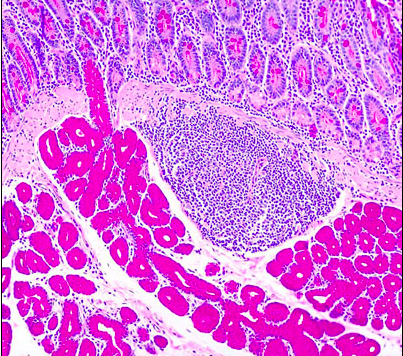

name this region of the intestine [1]

how can you tell [1]

jejunum

plicae circularis

Plicae circulares are out foldings of both the mucosa and submucosa. Projecting from these folds are numerous villi that are outfoldings of the mucosa.